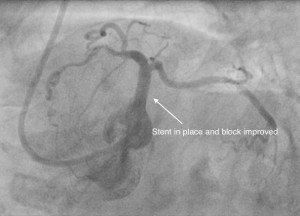

Left main coronary artery is the main artery in the left side that divides into two branches which supplies blood to most part of the heart. There are situations in which this is severely narrowed or blocked and would need attention. Previously, most patients were sent for coronary artery bypass surgery, but with advances in stent technology and the expertise available, angioplasty with stents are more and more performed nowadays to treat this condition. This can also be done, if the patients are considered too high risk for surgery or in emergency situations. Considering this is the largest coronary artery in the heart, it needs special attention and assessment to do the procedure to obtain excellent result.